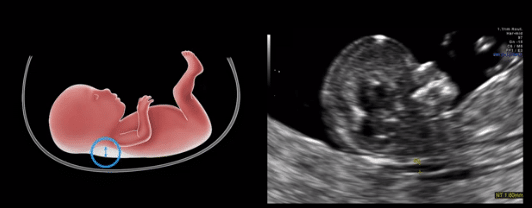

A Translucência Nucal é uma camada de fluido que se acumula na região da nuca do feto durante o primeiro trimestre da gravidez. O acúmulo de fluido é uma ocorrência normal, mas um aumento anormal da medida da TN pode estar associado a algumas condições genéticas.

A medida da TN é realizada durante o exame de ultrassom obstétrico, normalmente entre a 11ª e a 13ª semana de gestação. Neste período, a nuca do feto ainda é translúcida o suficiente para que a medida seja feita com precisão.

- Calipers: “ON-to-ON”, ou seja, devem coincidir com as linhas ecogênicas..